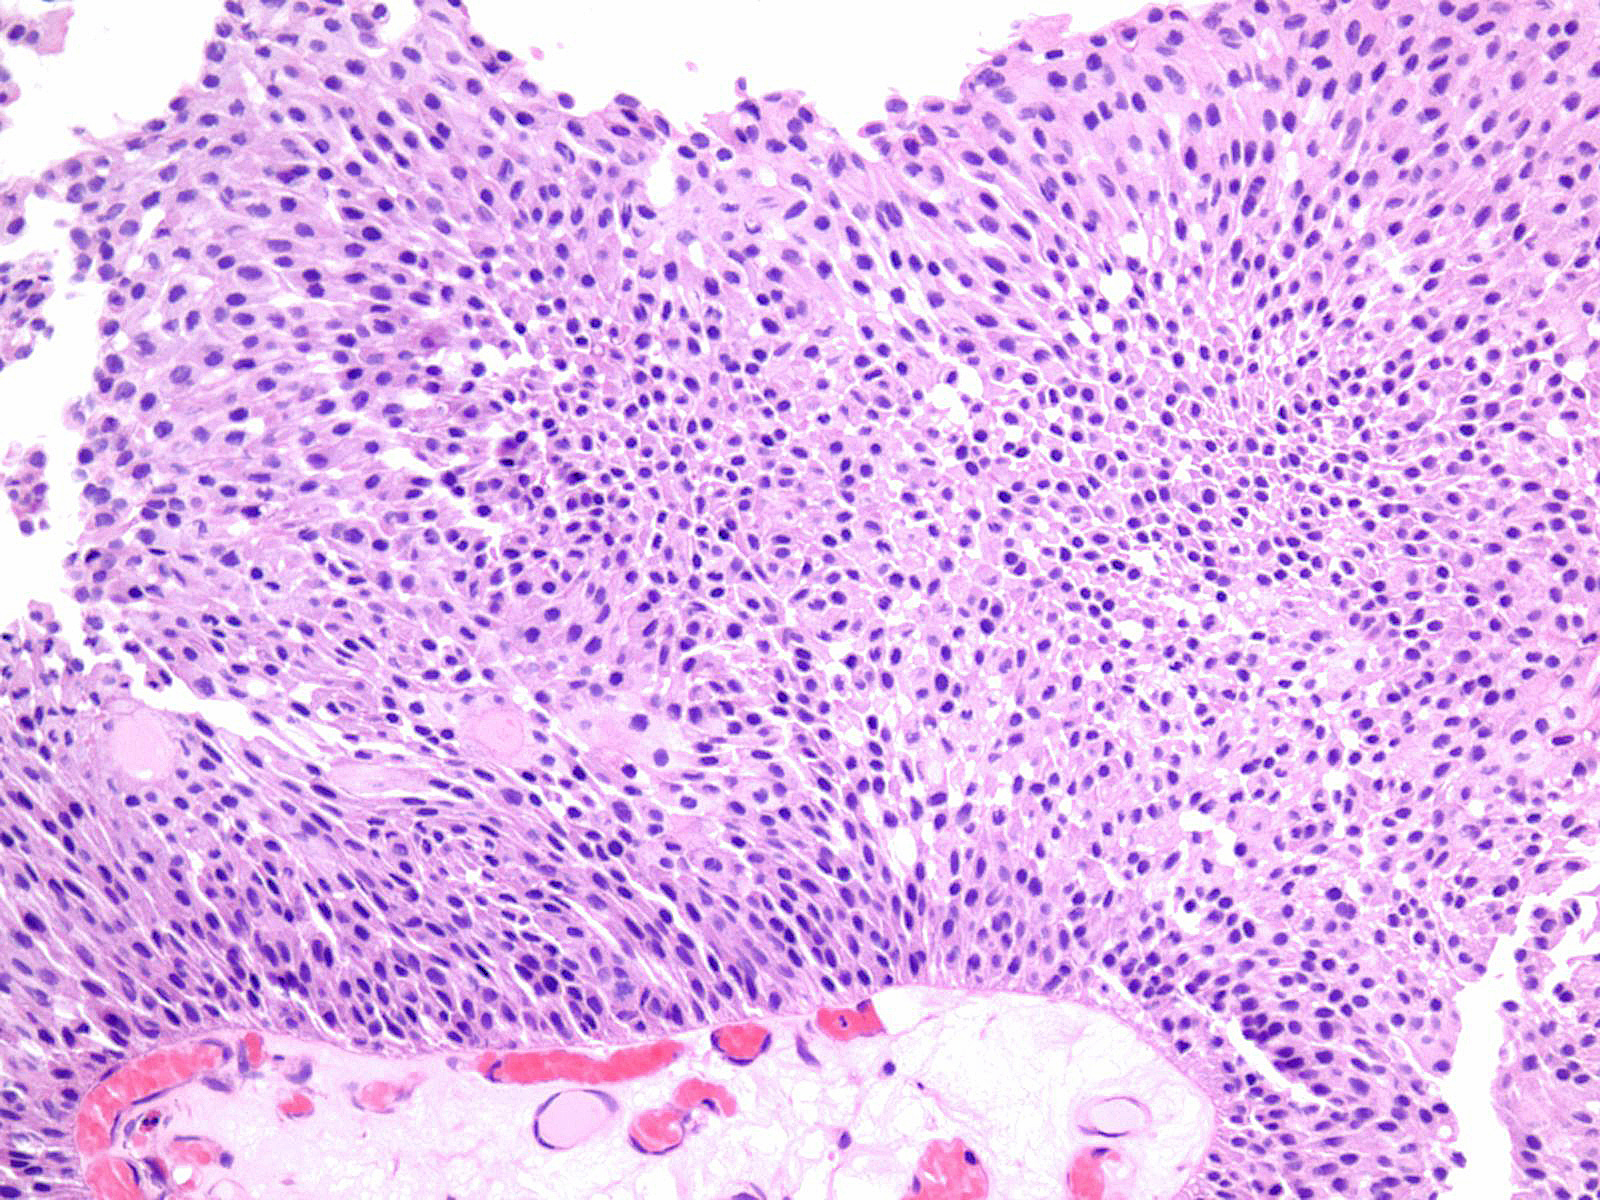

Consensus grade: Low-grade papillary urothelial carcinoma (LG-PUC)

Lesion shows moderate variation in nuclear size, shape and chromatin. Scattered nuclei are significantly enlarged and hyperchromatic relative to other nuclei. Lesion still maintains an overall orderly appearance.